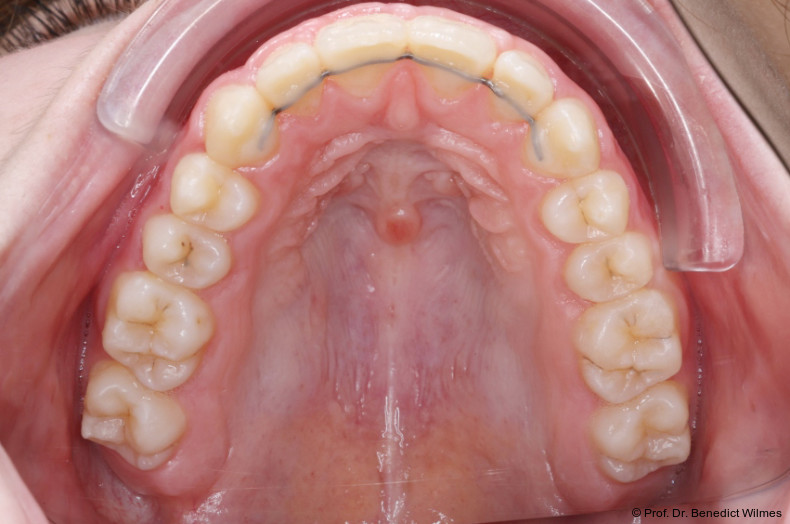

Die initiale Behandlung erfolgte mit einer CAD/CAM Hybrid Hyrax zur Expansion des Oberkiefers, verankert an zwei paramedianen Miniimplantaten (Abb. 4, Benefit, 2,0 x 9,0 mm). Anstelle klassischer Molarenbänder wurden Shells (geklebte Kappen) verwendet, wodurch die beiden Schritte Separieren und Anpassen von Molarenbändern entfallen. Die Miniimplantate und die Apparatur wurden dank eines Inser­tionsguides in nur einer Sitzung eingesetzt.

Die Shells wurden mit lichthärtendem Kom­posit befestigt. Nach Expansion des Oberkiefers (Abb. 5a–f) erfolgte eine Retentionsphase von neun Monaten, in der die Hybrid Hyrax in situ belassen wurde.